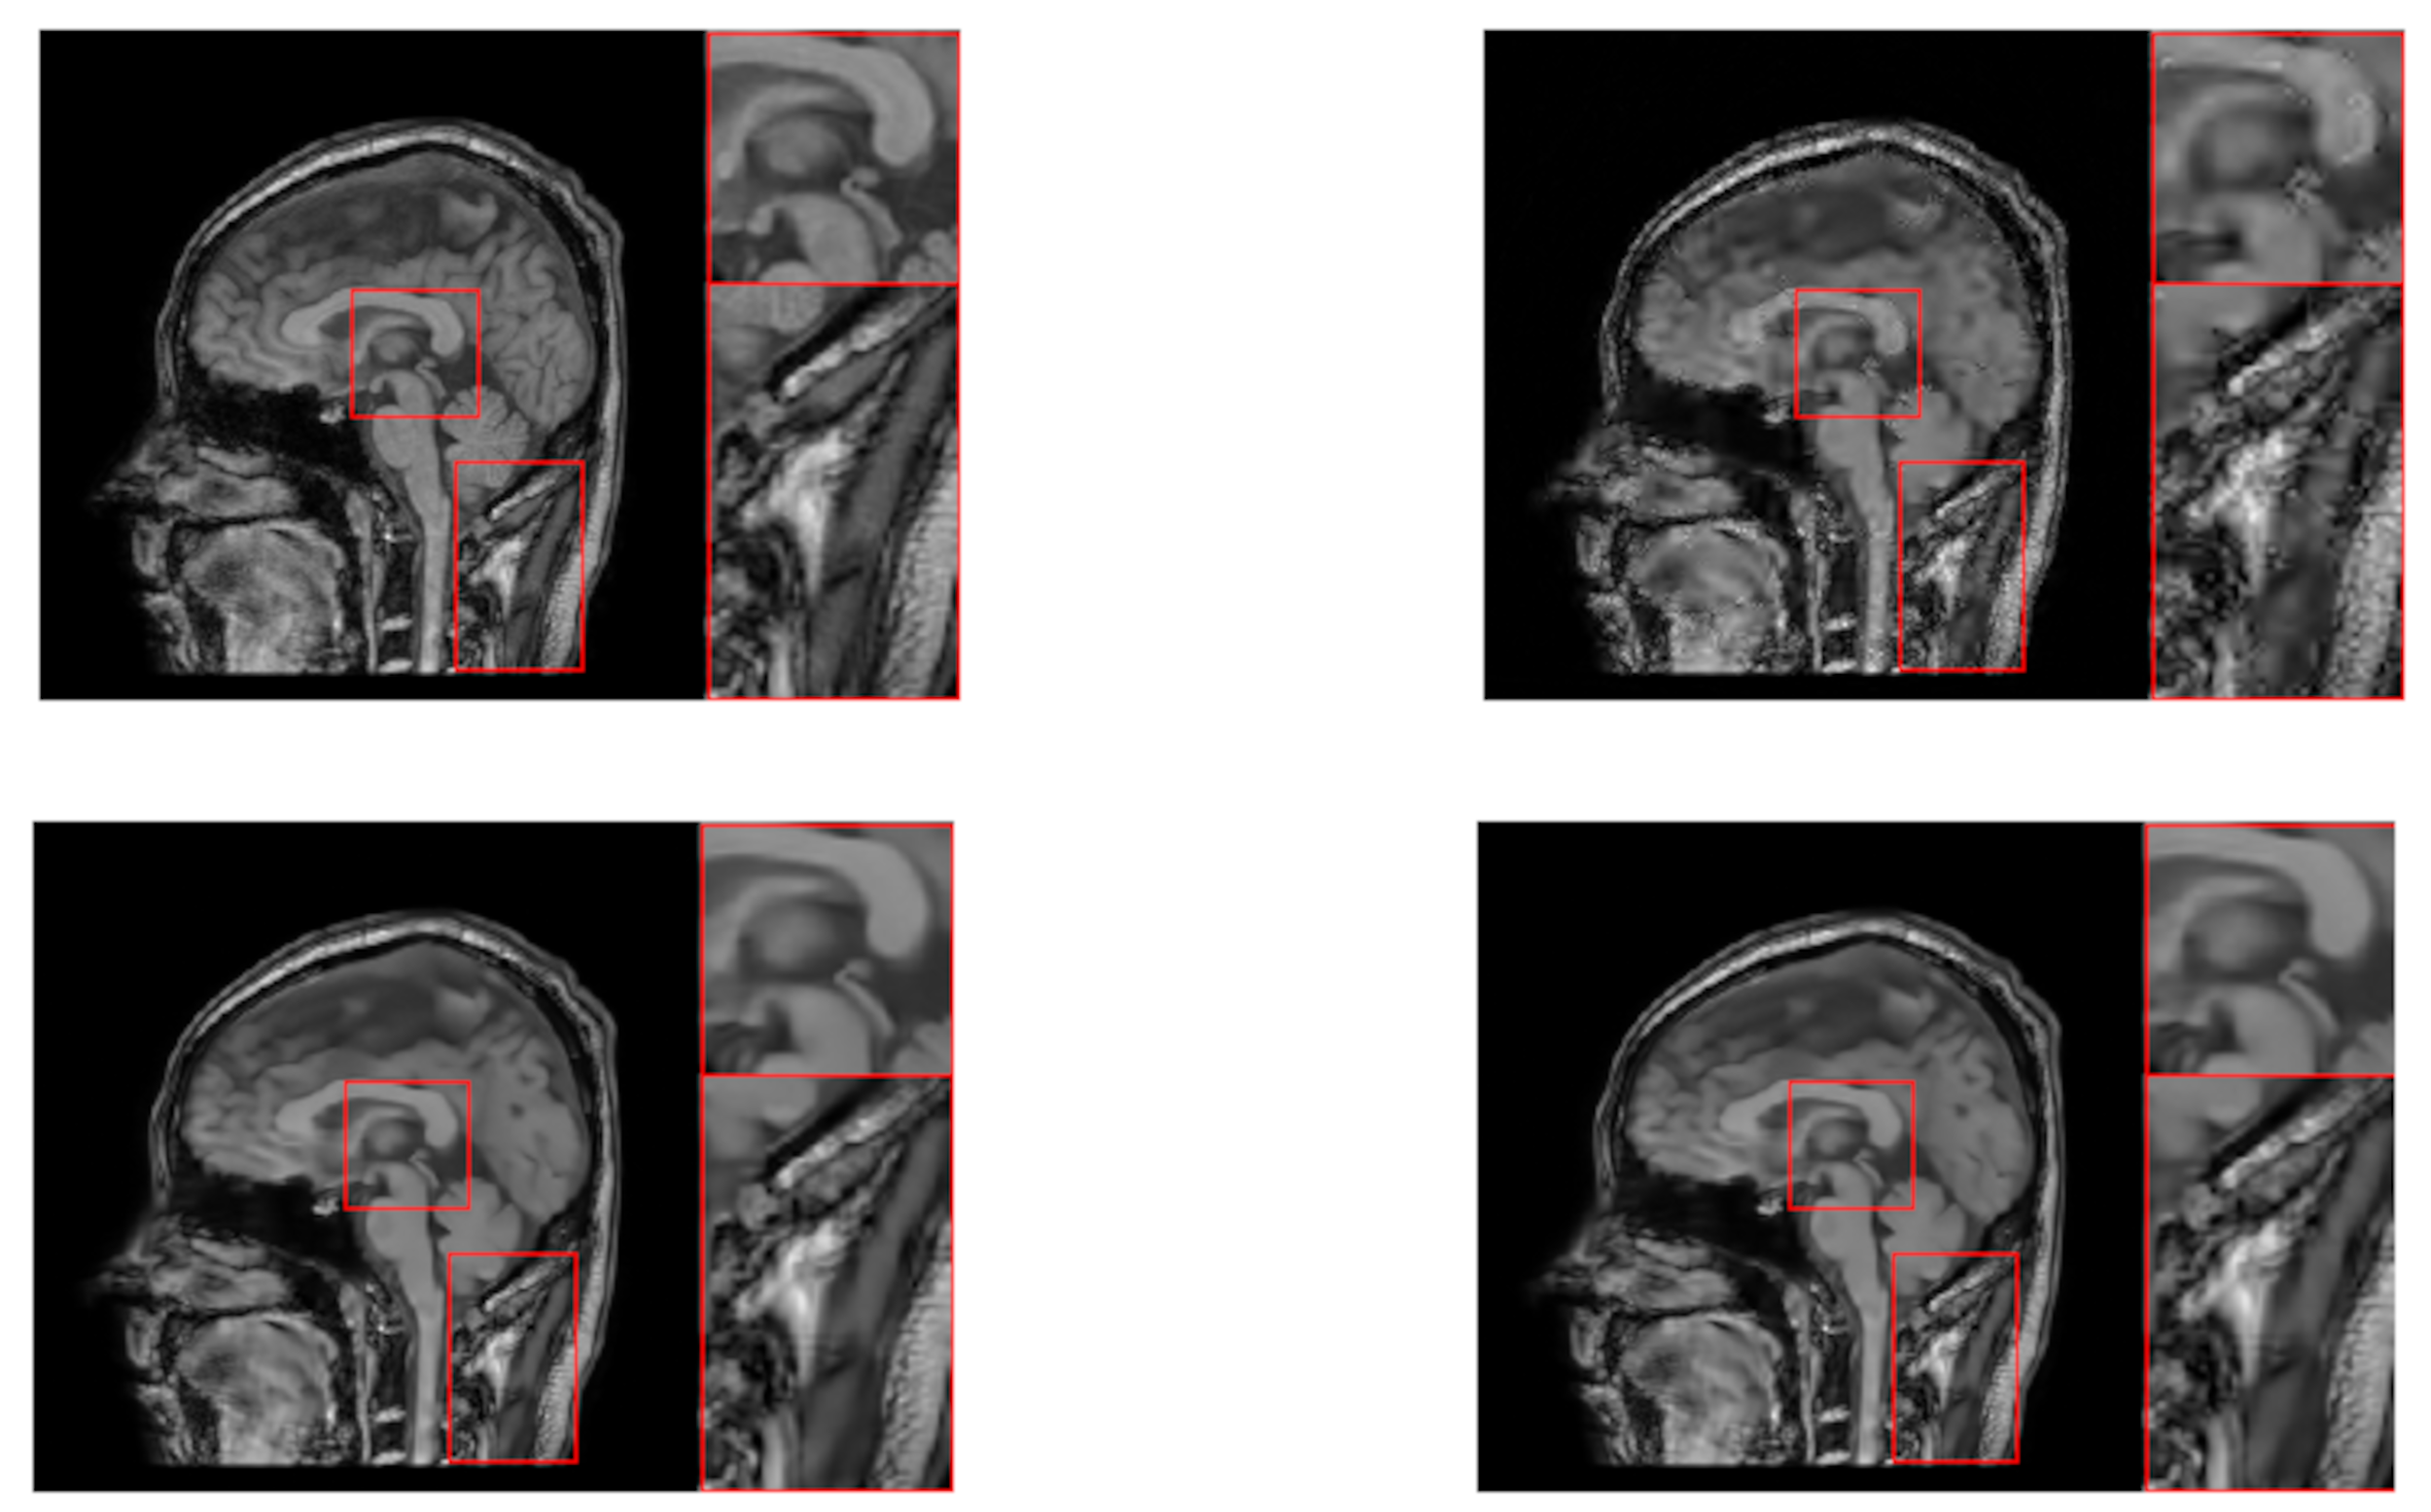

4. Experiments

| “brain” | ||||||||||||

| SRD-DDTF | NLR-DDTF with | NLR-DDTF with | ||||||||||

| err | corr | psnr | time | err | corr | psnr | time | err | corr | psnr | time | |

| 15 | 23.87 | 95.51 | 28.73 | 476.95 | 22.87 | 95.88 | 29.10 | 909.44 | 22.50 | 96.02 | 29.24 | 1553.29 |

| 30 | 15.57 | 98.12 | 32.44 | 944.79 | 12.34 | 98.82 | 34.46 | 1284.81 | 12.09 | 98.87 | 34.63 | 2059.53 |

| 45 | 12.97 | 98.70 | 34.03 | 1390.10 | 9.31 | 99.33 | 36.91 | 1728.38 | 9.22 | 99.34 | 36.99 | 2453.39 |

| 60 | 11.60 | 98.96 | 35.00 | 1777.77 | 7.51 | 99.56 | 38.77 | 2112.93 | 7.45 | 99.57 | 38.84 | 2838.36 |